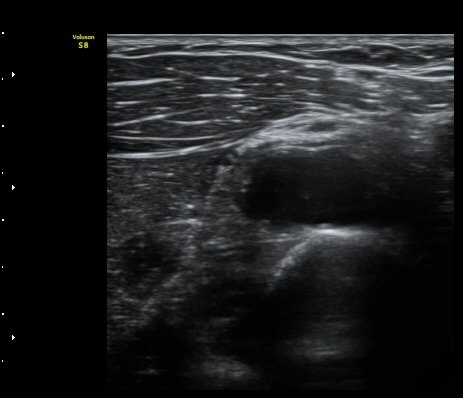

ŽÃËÀÚ¸¦ Á» ´õ ¸»´ÜÀ¸·Î À̵¿ÇÏ´Ï ³¶Á¾Àº ´õ Å©°Ô °üÂûµÈ´Ù(±×¸² 3, 4).

¿ä°ñÀ» Á¾´Ü¸éÀ¸·Î °üÂûÇÏ´Ï ¿ä°ñ ±ÙÀ§ºÎ Ç¥Ãþ¿¡ ³¶Á¾ÀÌ È®Àεǰí(±×¸² 5) ŽÃËÀÚ¸¦

Á¶ÀýÇÏ´Ï Èİñ°ß½Å°æÀÇ Á¾´Ü¸é À̹ÌÁö°¡ °üÂûµÇ´Âµ¥ ³¶Á¾¿¡ ÀÇÇØ Ç¥ÃþÀ¸·Î ÀüÀ§µÇ¾î

ÀÖ´Ù(±×¸² 6,7). ±×¸² 8. ³¶Á¾°ú Èİñ°£½Å°æ ÁÖÀ§¾Ö¼­ °üÂûµÇ´Â µ¿¸Æ.